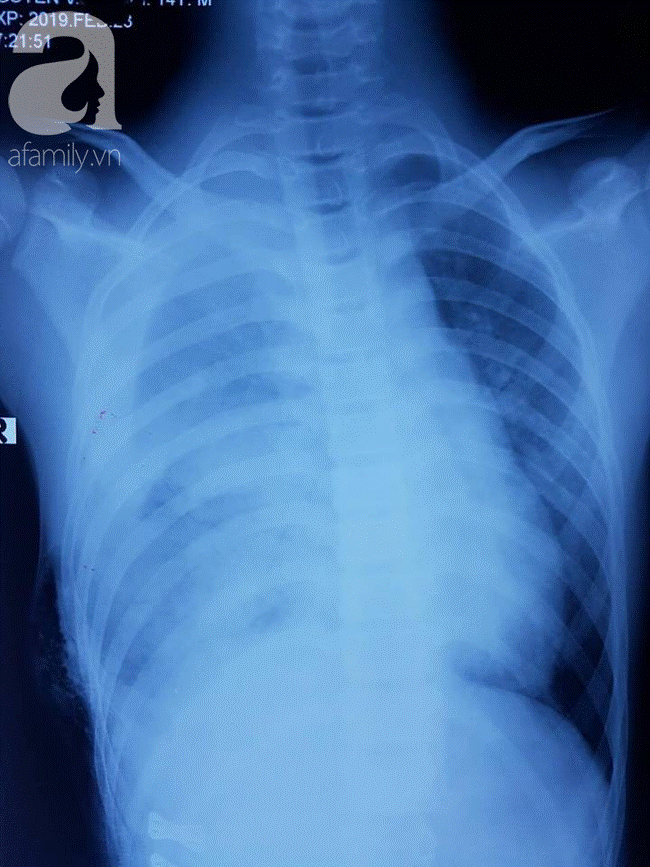

Ảnh chụp X-quang cho thấy bé bị xẹp một bên phổi.

Bệnh nhân nhập viện trong tình trạng doạ sốc mất máu, đa chấn thương nặng, mạch nhanh, huyết áp xu hướng tụt, tràn máu màng phổi nhiều làm xẹp hết 1 bên phổi gây suy hô hấp nặng nề